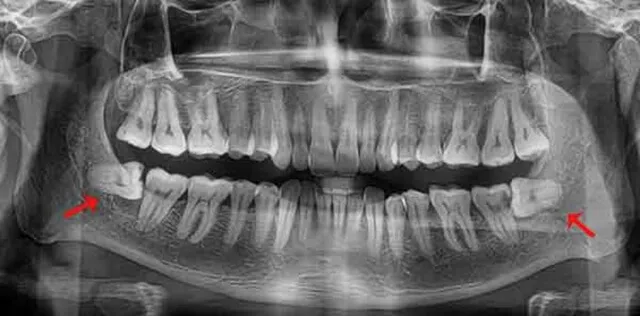

Răng khôn có thể mọc thẳng, mọc lệch, mọc ngầm hoặc mọc ngang. Răng mọc thẳng thường dễ nhổ, ít can thiệp nên chi phí thấp. Ngược lại, răng mọc lệch hoặc mọc ngầm cần tiểu phẫu, chi phí cao hơn để đảm bảo an toàn.

Những trường hợp răng khôn viêm nhiễm, sát dây thần kinh hoặc sát xoang hàm đòi hỏi bác sĩ phải thăm khám kỹ lưỡng, chụp phim X-quang và xử lý cẩn trọng, từ đó làm tăng chi phí điều trị.